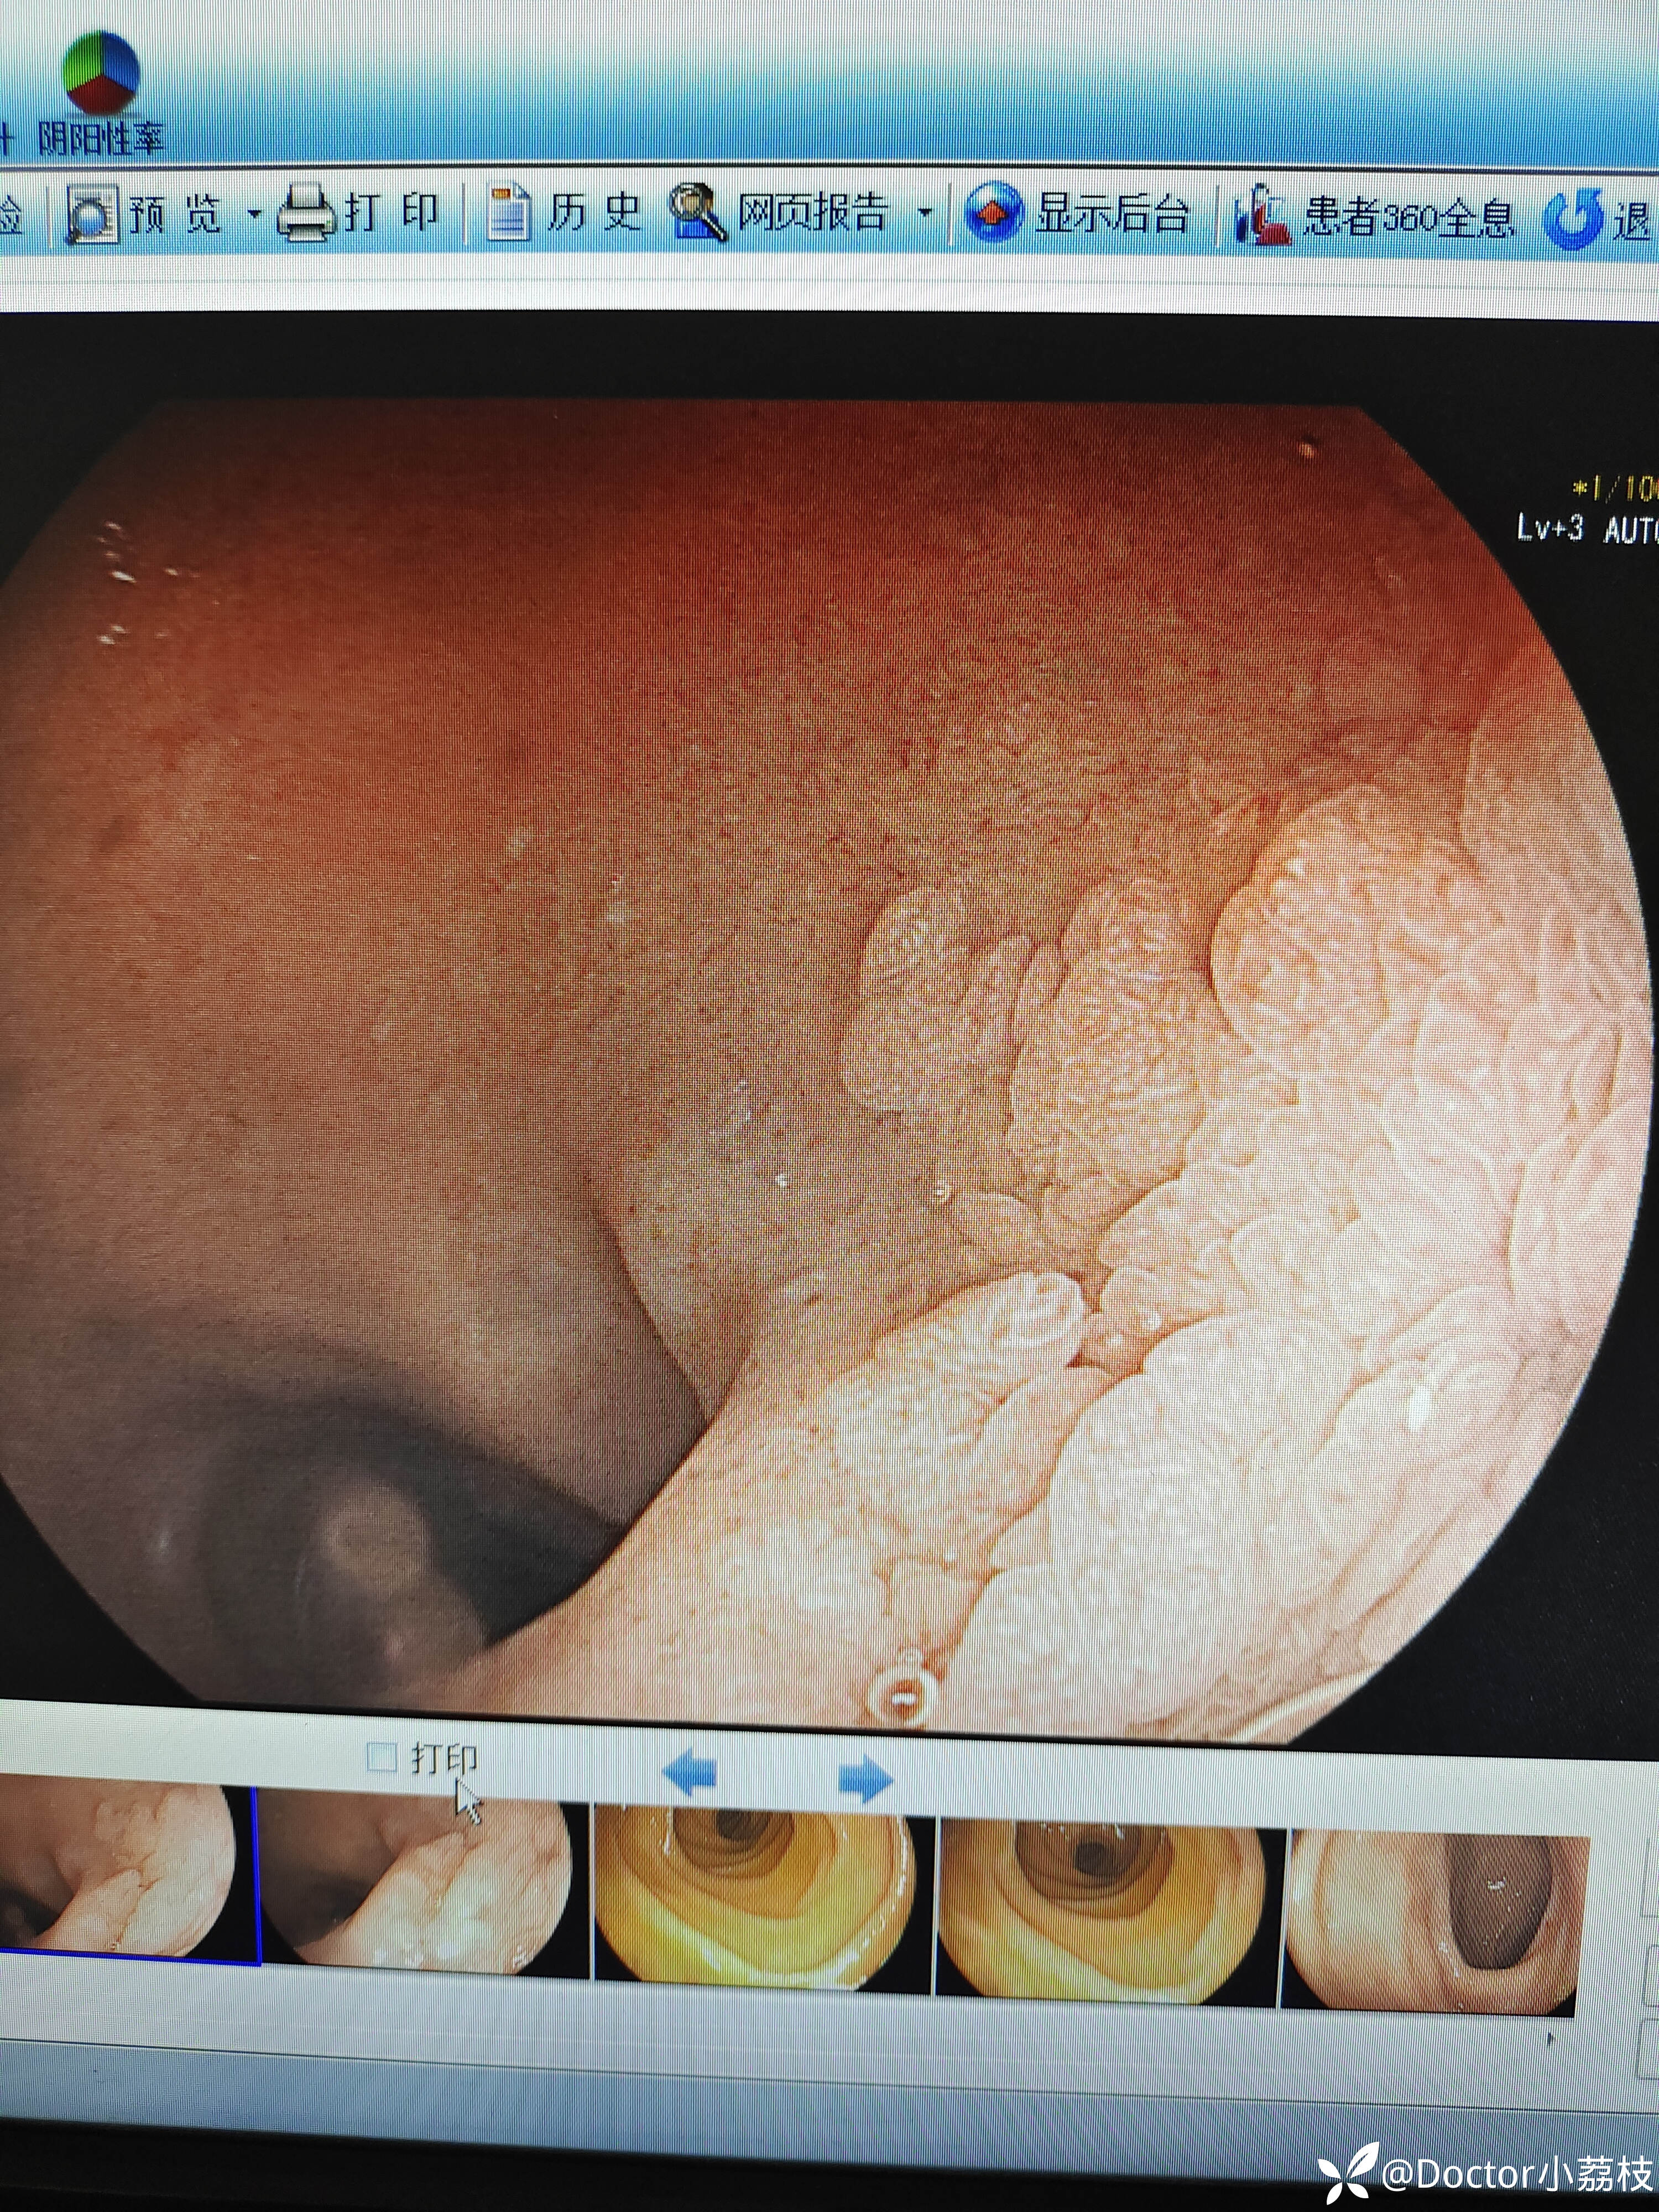

今天做胃镜发现的,患者因胆囊结石于肝胆外科就诊,拟行腹腔镜下胆囊切除,自诉两日前黑便一次,此后大便转黄。今日行胃镜见12指肠后壁病变。我是胃镜初学,想请教各位前辈,这个病变考虑什么